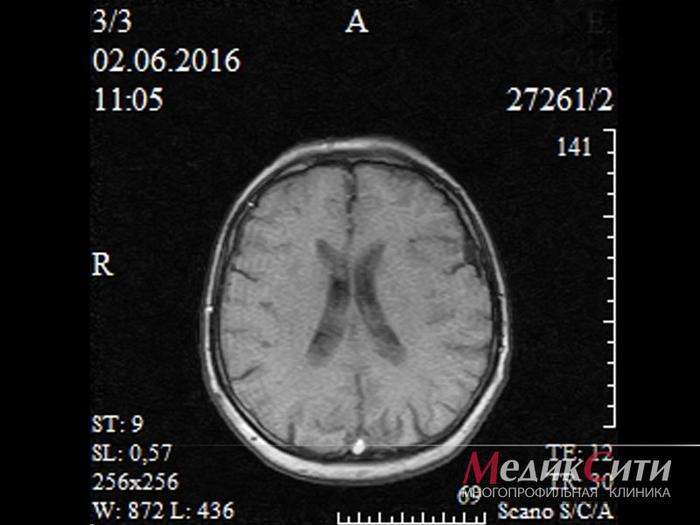

МРТ головного мозга

МРТ головного мозга

МРТ головного мозга